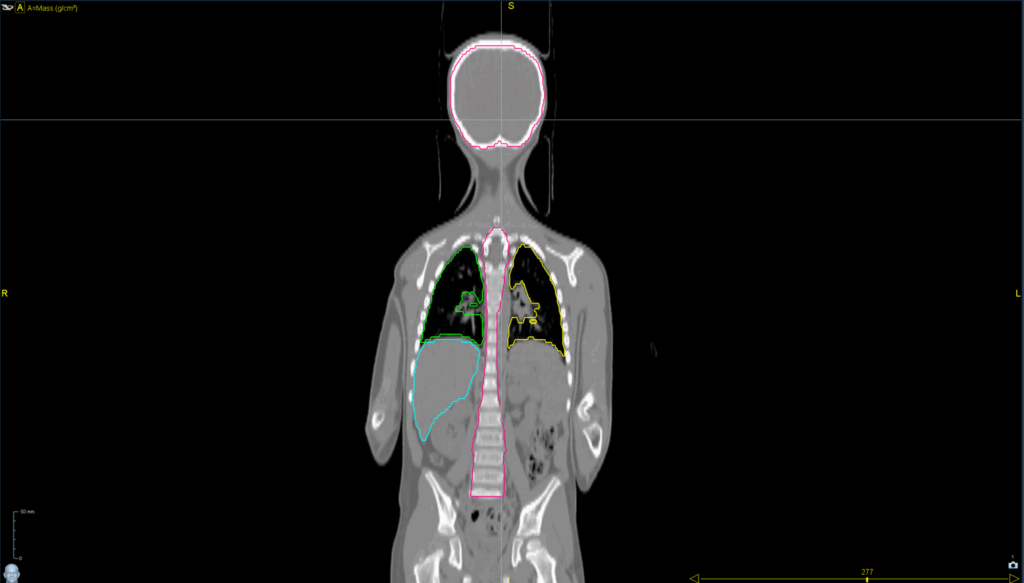

Planning CT Images

Treatment Plan Images